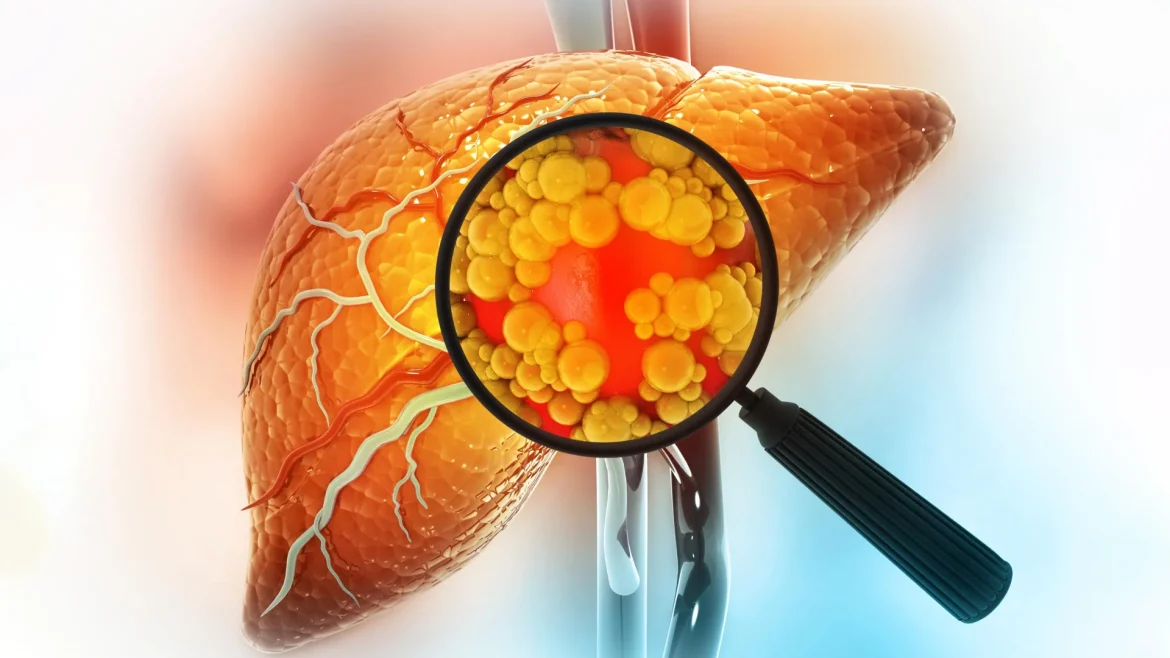

Uma dieta rica em gordura é um dos maiores contribuintes para o risco de câncer de fígado. Uma nova pesquisa do MIT esclarece por que isso acontece, mostrando que dietas gordurosas podem alterar fundamentalmente as células do fígado de forma a aumentar a probabilidade de desenvolvimento de câncer.

Dietas ricas em gordura podem causar inflamação e acúmulo de gordura no fígado, levando a uma condição conhecida como doença hepática esteatótica. Esta doença também pode surgir de estressores metabólicos de longo prazo, como o consumo excessivo de álcool, e pode progredir para cirrose, insuficiência hepática e, por fim, câncer.